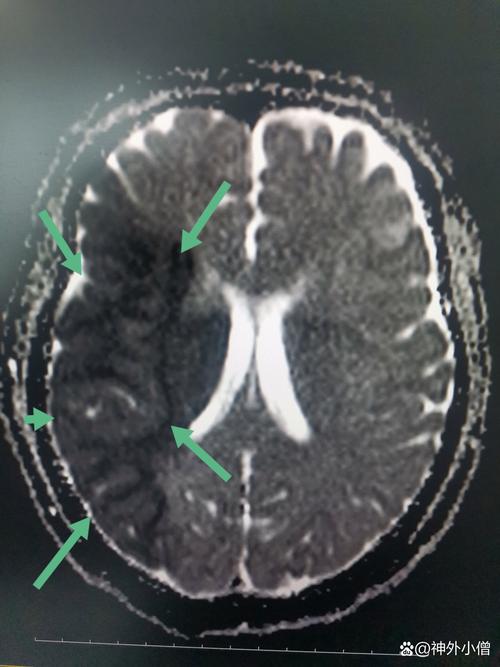

堵塞脑血管: 血栓会顺着血流,一直冲向大脑,如果血栓的体积较大,或者脑血管本身就有狭窄,它就会在某个关键的脑血管处(如大脑中动脉)被卡住,造成血管的急性、完全性堵塞。

- 大脑中动脉是供应大脑半球最主要的血管之一,它堵塞后,会导致其供应的大面积脑组织严重缺血、缺氧。

- 脑细胞对缺氧极其敏感,在几分钟内就会开始死亡,这种死亡是不可逆的。

- 导致大面积脑梗死,这是一种极其凶险的卒中类型。